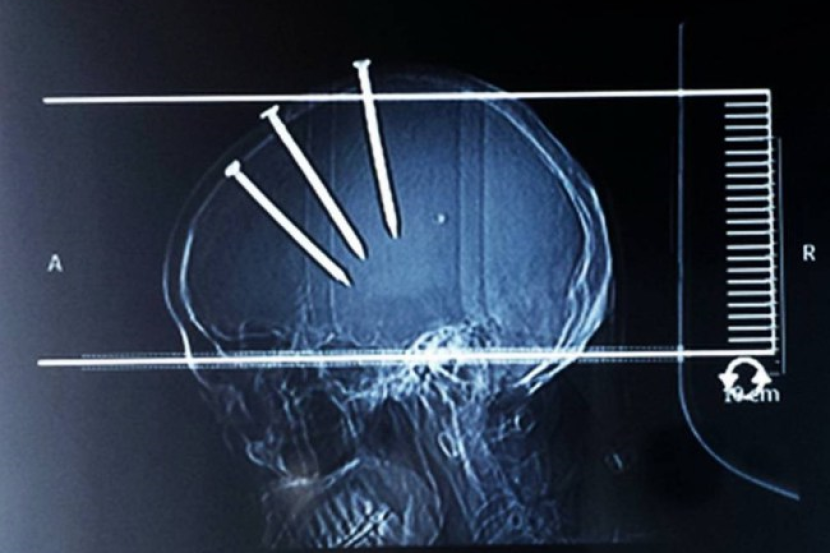

FUJIAN, CHINA: Seorang lelaki berusia 69 dianggap bertuah kerana masih mampu hidup selepas memaku kepalanya dengan tiga batang paku sepanjang 10 sentimeter setiap satu.

Hasil imbasan x juga mendapati paku tersebut tertanam kemas di kepala mangsa bagaimanapun tidak memberikan sebarang kecederaan serius kerana kedudukannya di kawasan selamat.

Warga emas itu telah menjalani pemulihan sejak tiga bulan lalu di sebuah hospital di Haifeng di sini sebelum dibenarkan keluar dalam keadaan sihat apabila paku berkenaan berjaya dibuang.